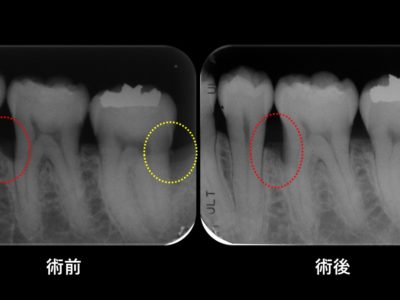

30代女性 主訴:歯茎から血が出る 術前 歯周ポケット(歯と歯茎の間の溝の深さ)が正常値(2-3㎜)を超えて部分的に5-8㎜程度にまで及んでいました。レントゲンから歯を支えている歯槽骨という骨が歯周病によって吸収を起こしていることが判ります。なるべく侵襲の少ない(切開の範囲の狭い)方法で歯周外科手...

30代女性 主訴:歯茎から血が出る 術前 歯周ポケット(歯と歯茎の間の溝の深さ)が正常値(2-3㎜)を超えて部分的に5-8㎜程度にまで及んでいました。レントゲンから歯を支えている歯槽骨という骨が歯周病によって吸収を起こしていることが判ります。なるべく侵襲の少ない(切開の範囲の狭い)方法で歯周外科手...